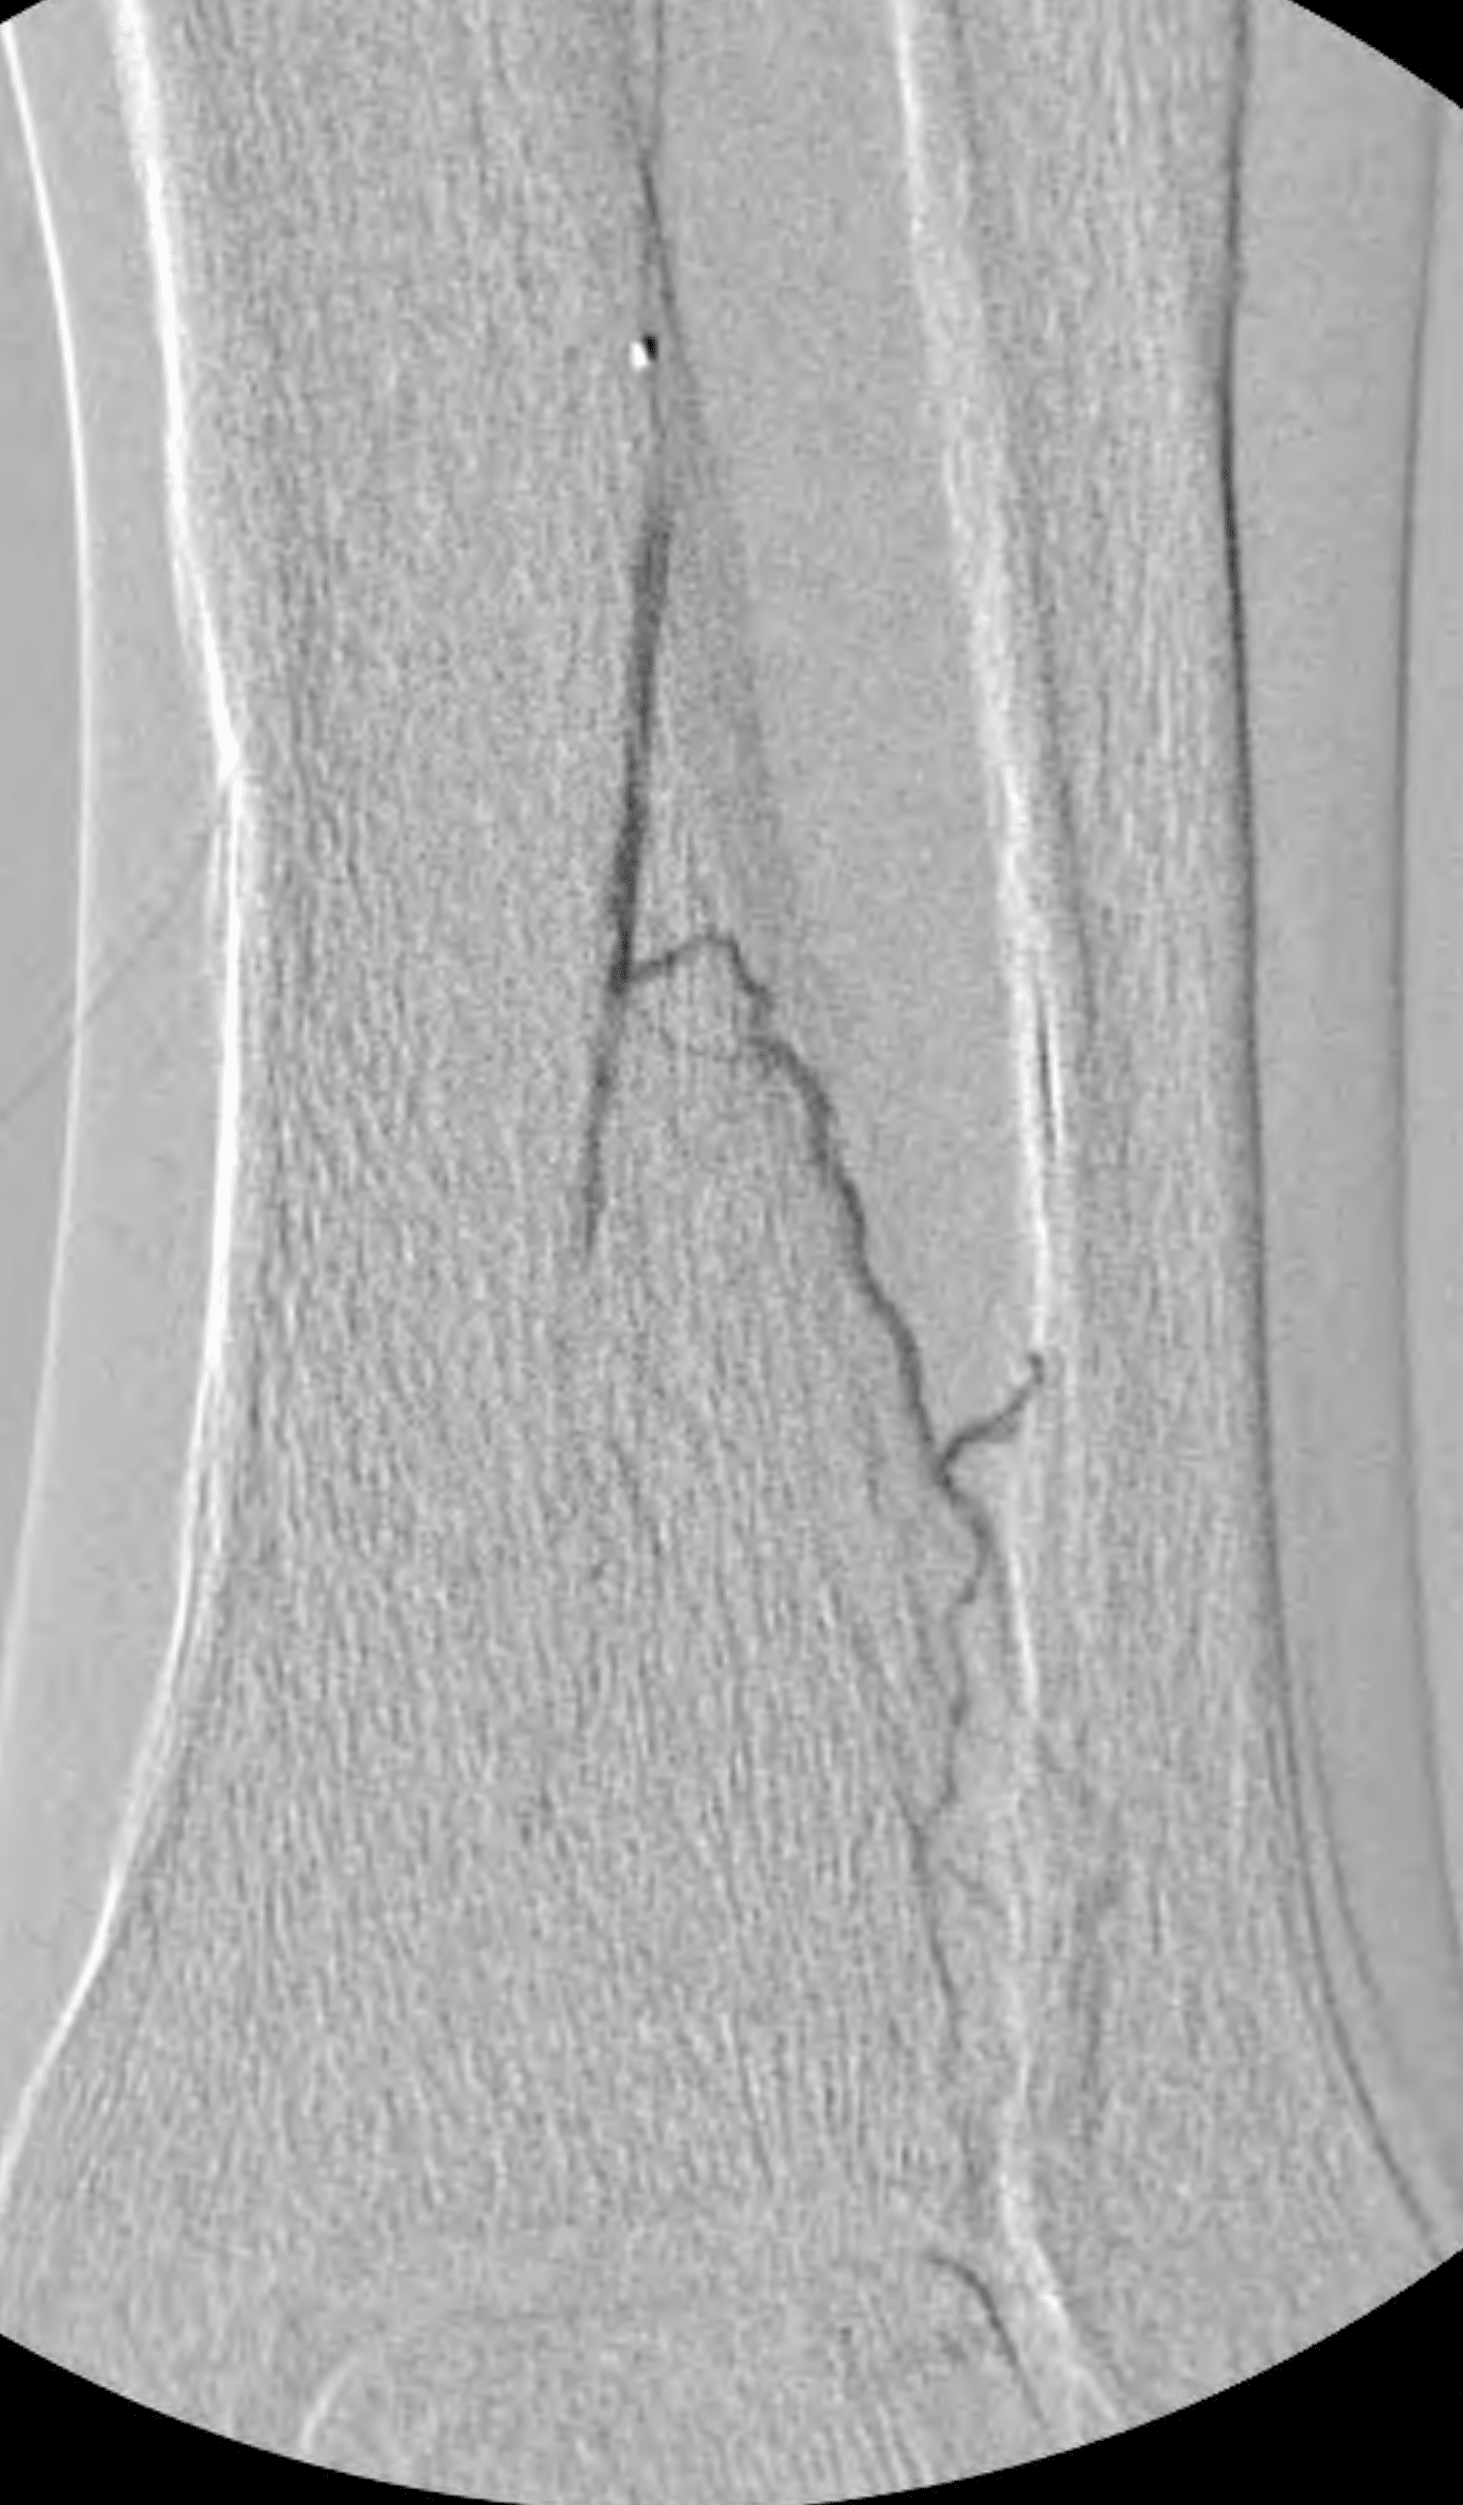

Accessing the occluded segment of an artery has been referred to as the modified Schmidt technique. Real-time ultrasound guidance is useful to accomplish this. After a needle was directed into the occluded anterior tibial artery and visualized within its lumen, a wire was successfully advanced through the occlusion in retrograde fashion into the more proximal anterior tibial artery true lumen. A 2-mm balloon was then advanced “bareback” into the distal occluded segment of the anterior tibial artery and angioplasty was performed (Figure 7). The balloon was withdrawn.

This allowed antegrade advancement of a wire from the “up and over” access into the further distal anterior tibial artery. However, it was still not possible to advance a catheter in antegrade fashion into the true lumen dorsalis pedis artery. Therefore, another retrograde access was obtained—this time, into the patent reconstituted dorsalis pedis artery (Figure 8).